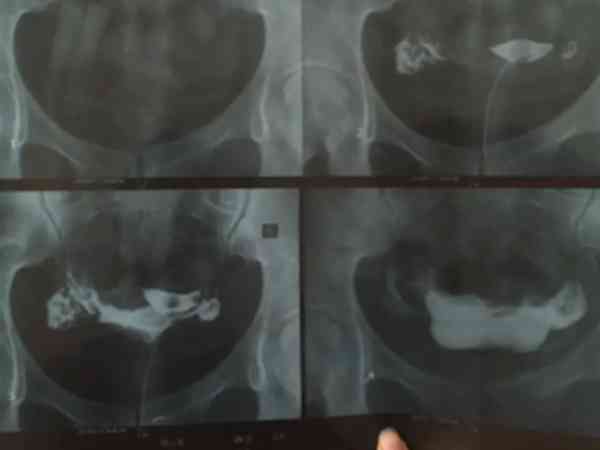

一般來說,做完造影后需要等待1-2個月,才可以進行輸卵管疏通手術。造影是一種檢查輸卵管通暢情況的方法,通過注入造影劑,可以觀察造影劑在輸卵管內的流動情況。輸卵管造影檢查後需要根據患者恢復情況再來決定合適的時間來做宮腔鏡下通水術,一般是在下個月經週期就可以做,就是在月經乾淨後,複查白帶正常,無盆腔感染的情況下做通水術就比較好。輸卵管造影檢查分為碘油造影和超聲造影,都需要使用到造影劑,很多患者做完造影后身體會不舒服,所以需要根據恢復時間來決定做通水手術的時間。

輸卵管造影檢查是不孕症的檢查專案之一,主要檢查輸卵管是否通暢,造影不能確診,只是參考,宮腹腔鏡檢查才能確診。一般是建議做宮腹腔鏡檢查術,檢查了再根據情況進行通水處理。當做完造影后多久可以做通水術,情況如下: